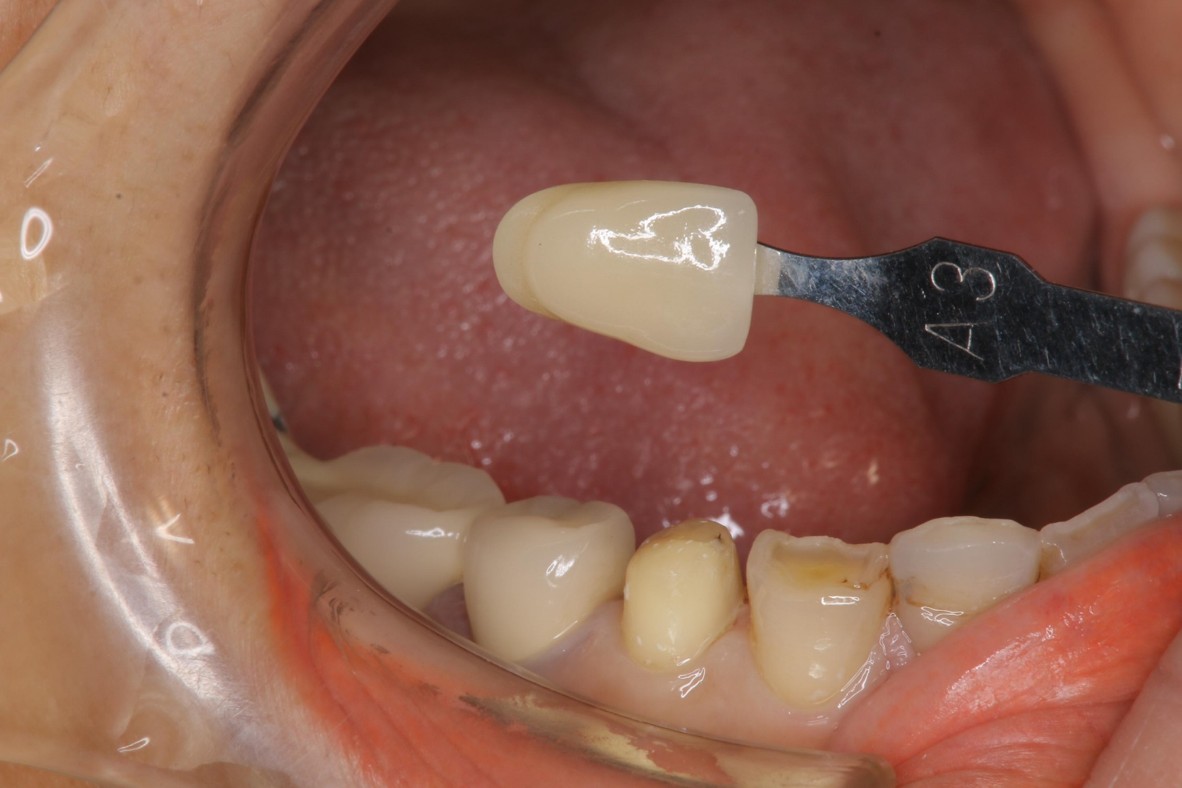

照相比色